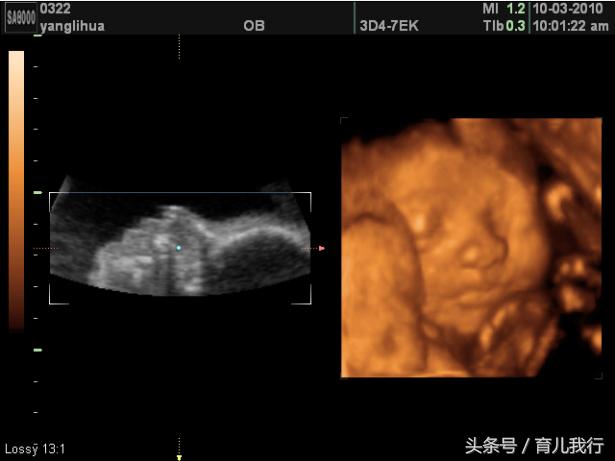

今天是怀孕的第六个月了,去医院照了四维,糖筛检查也顺利通过了,后来跟医生确认了一下胎儿的性别,原来是小公举哦!终于也是如我所愿了。

15周的时候就感受到了胎动,期间我做过一次飞机,医生说三个月前坐飞机的话宝宝容易没有胎心,他之前就有个病人做完飞机回来以后胎停了。又吓得我去医院照B超,还好宝宝没事,不然我真的是会后悔一辈子的。现在24周了,去医院照四维和做糖筛都通过了,宝宝也会侧身、转身之类的动作了,现在每天都能感受到他在里面活动。

很多人看见了都说我怀的是男孩,我胎梦的时候也梦过石榴和大*狗黑**,都是男孩的胎梦。去照四维的前一天梦见一朵很灿烂的向日葵,我妈说可能是女儿哦。然后四维的结果出来还真是小公举哦。